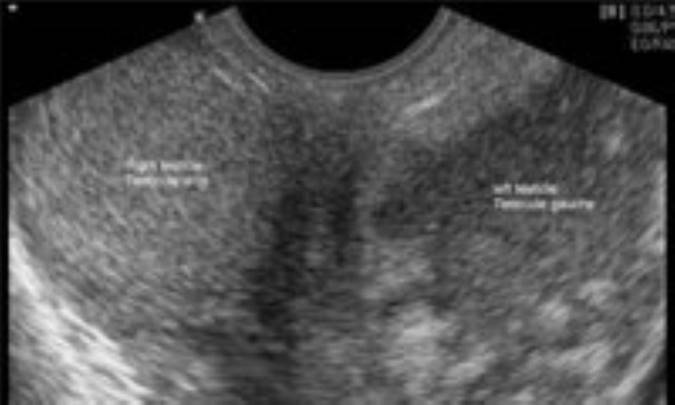

معمولاً تشخيص‌ تنها با معاينه‌ فيزيكي‌ گذاشته‌ مي‌شود ولي‌ سونوگرافي‌ نيز ممكن‌ است‌ انجام‌ شود.